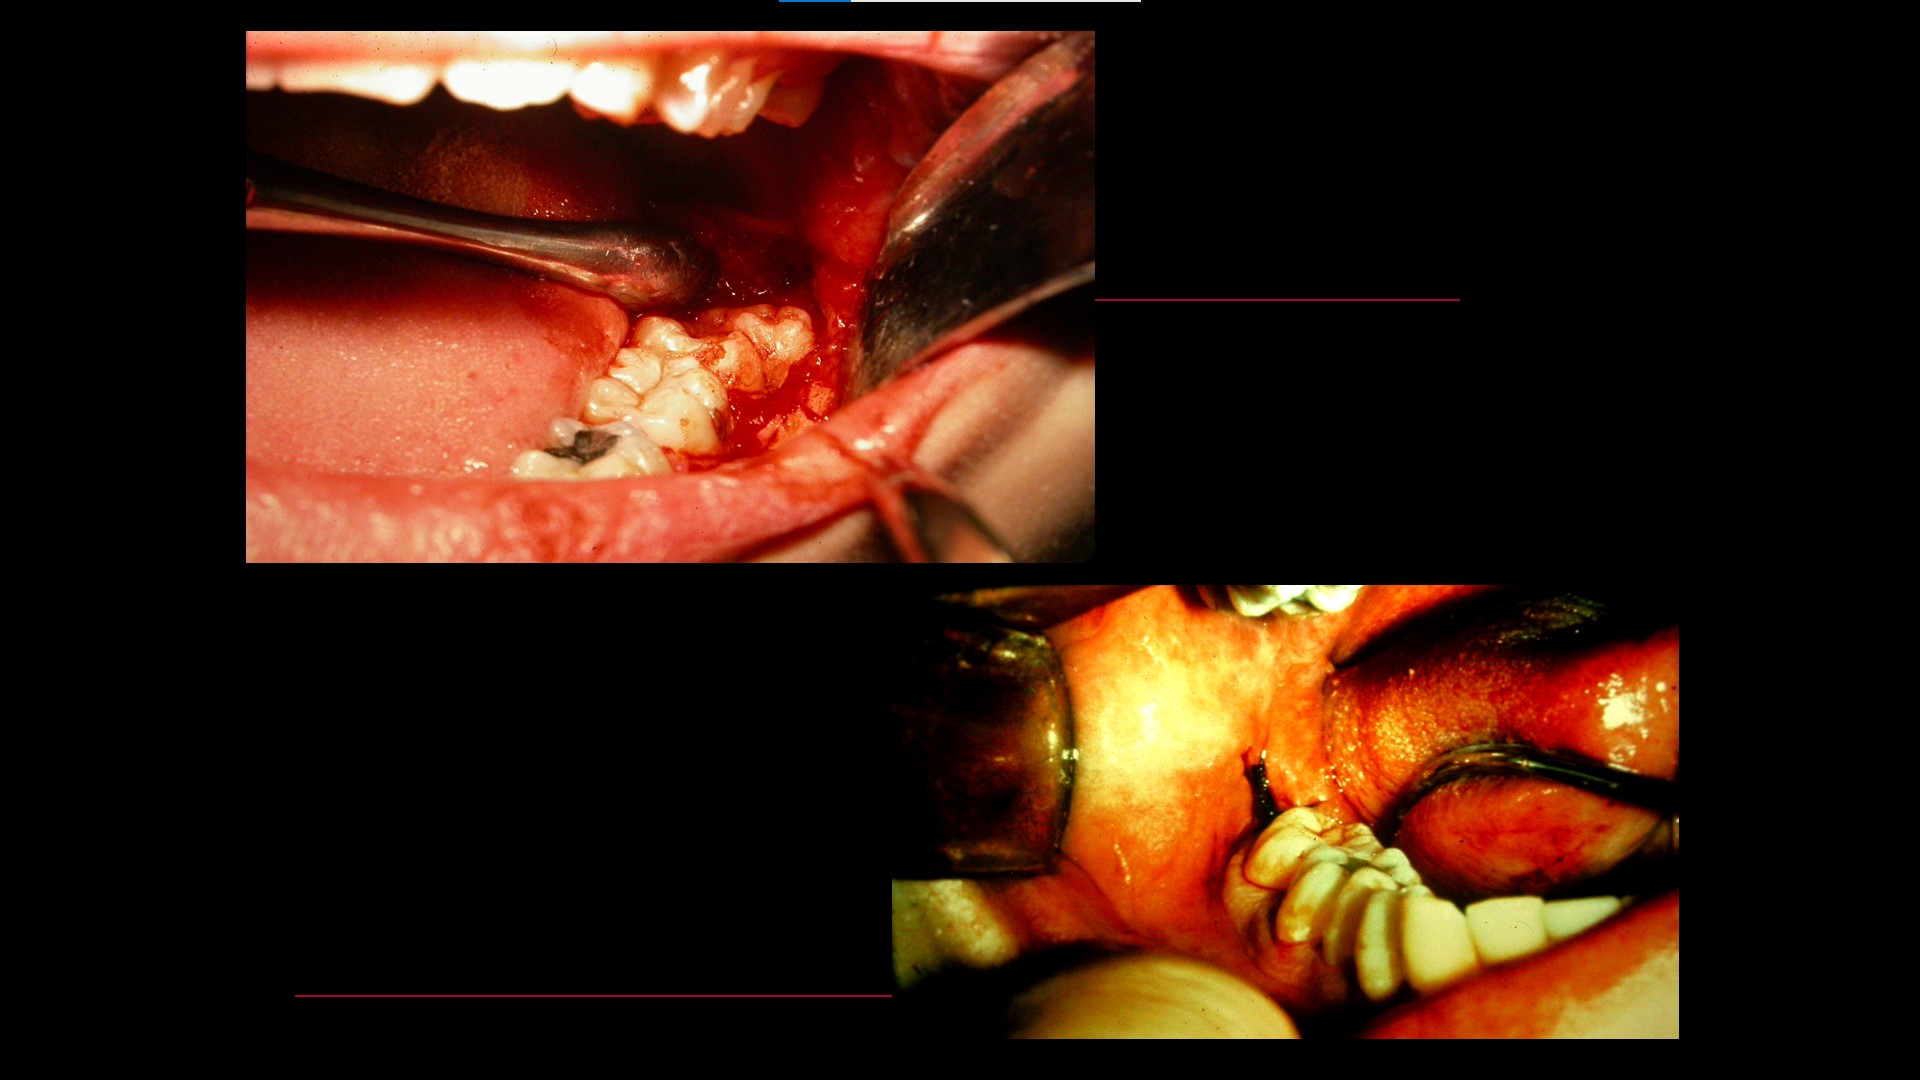

Impacted teeth

Oral Surgical Procedures